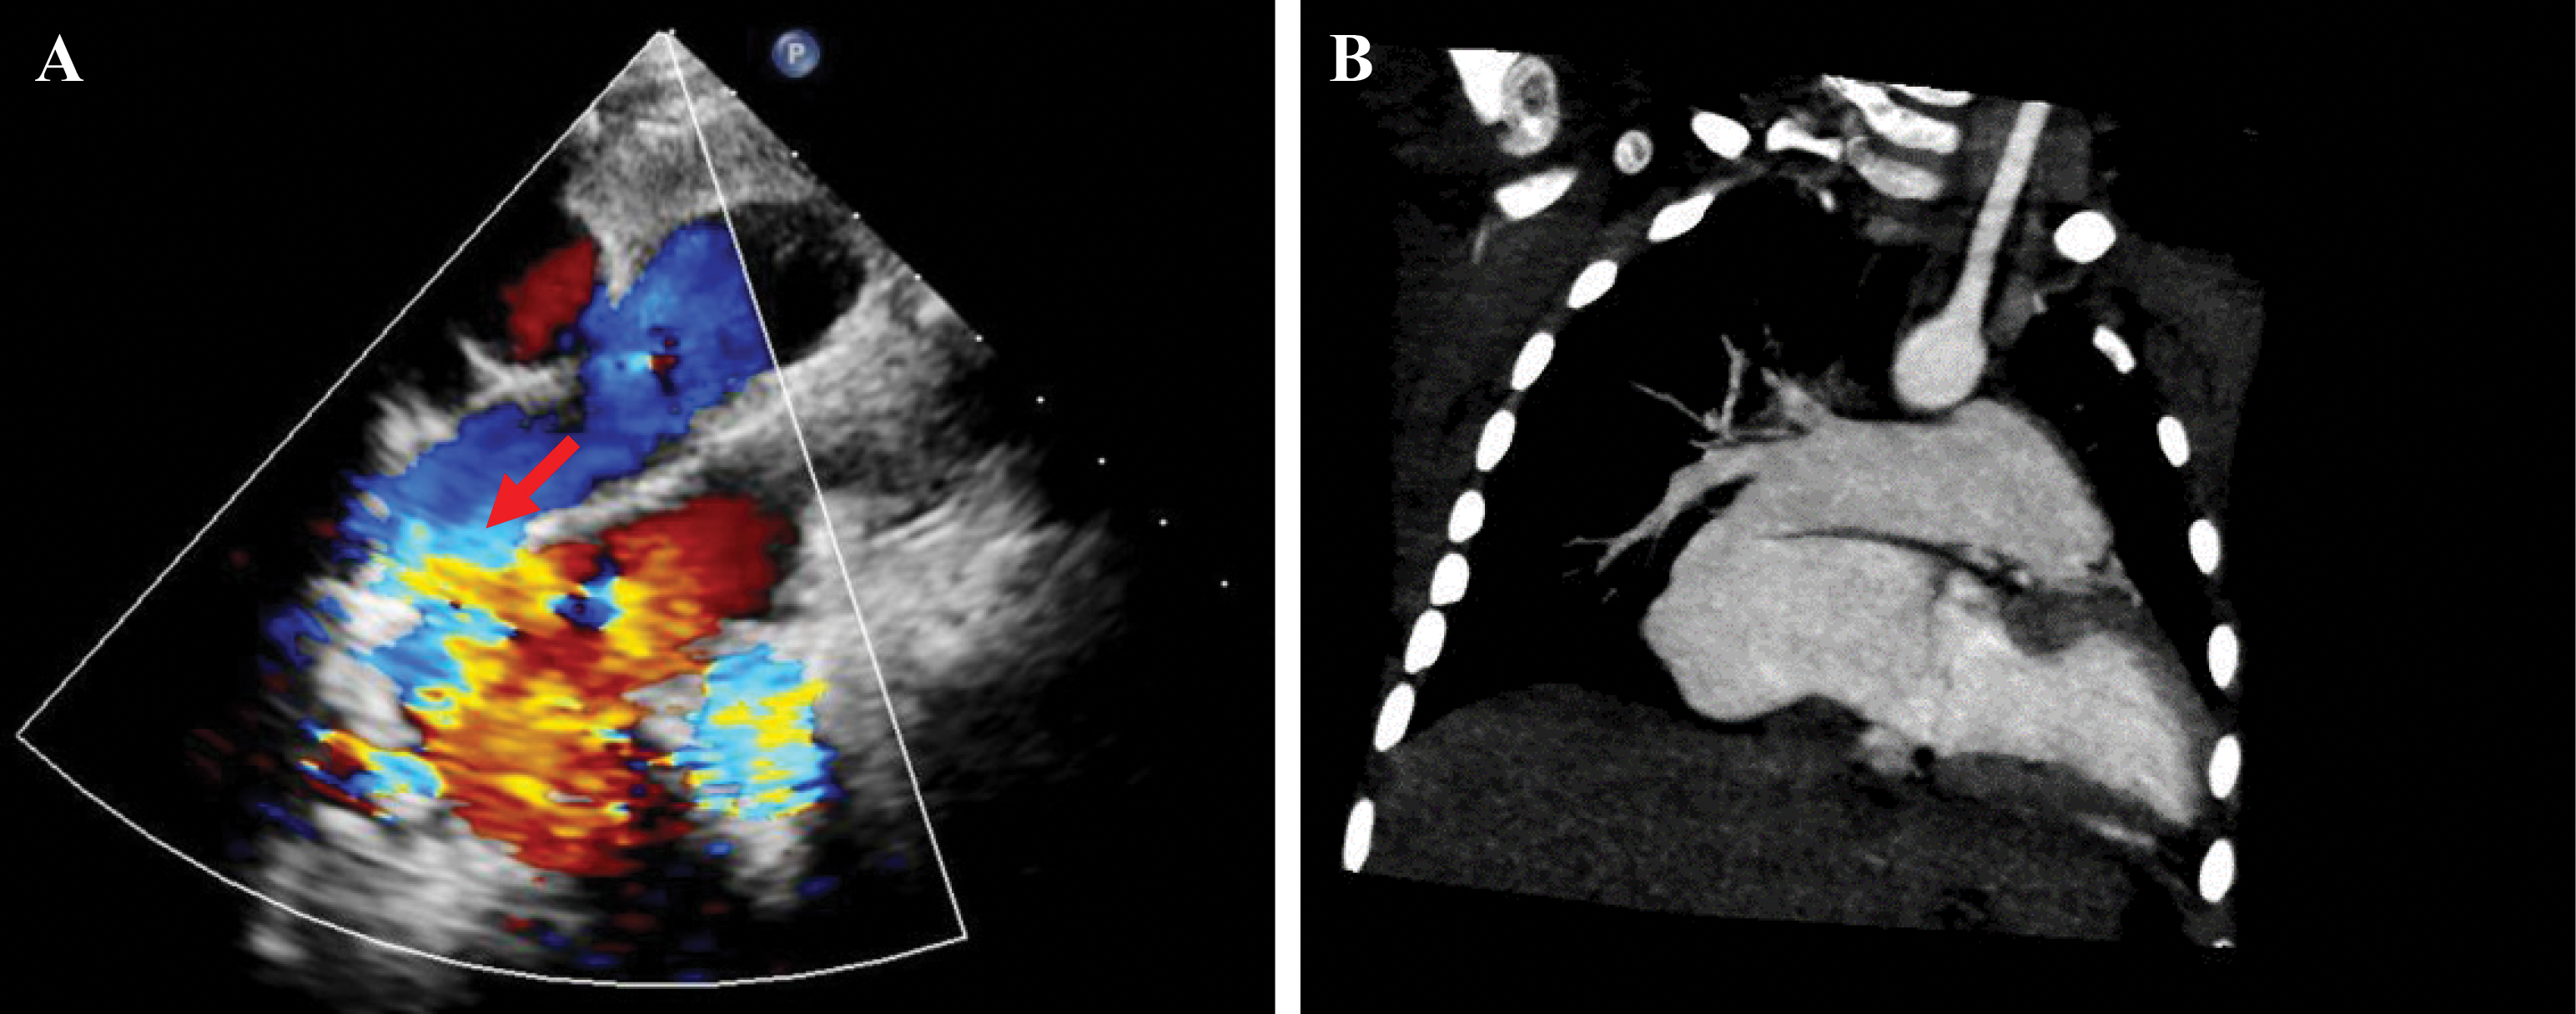

An electrocardiogram revealed sinus arrhythmia, and the electric axis deviated to the right. The echocardiogram showed a 7.8 mm × 7.2 mm secondary atrial septal defect (ASD) and a turbulent color flow Doppler in the LA, which made the shape of the LA, was “wired” (Fig. 1A). The left pulmonary artery diameter was 0.87 cm, while that of the right pulmonary artery (RPA) was 1.71 cm. The ultrasound confirmed that the pulmonary venous return and the left cardiac function were both normal. Computed tomography (CT) scan also revealed enlargement of the LA and ASD. The CT images displayed a fistula between the RPA and LA that was previously overlooked because of the lack of understanding of this rare disease (Fig. 1B).

Figure 1: Echocardiography and CT scan showing the fistula between the RPA and LA; however, it is usually overlooked. (A) Echocardiography reveals communication between the RPA and LA. The red arrow indicates the fistula. (B) CT can also show the direct communication between the PA and LA